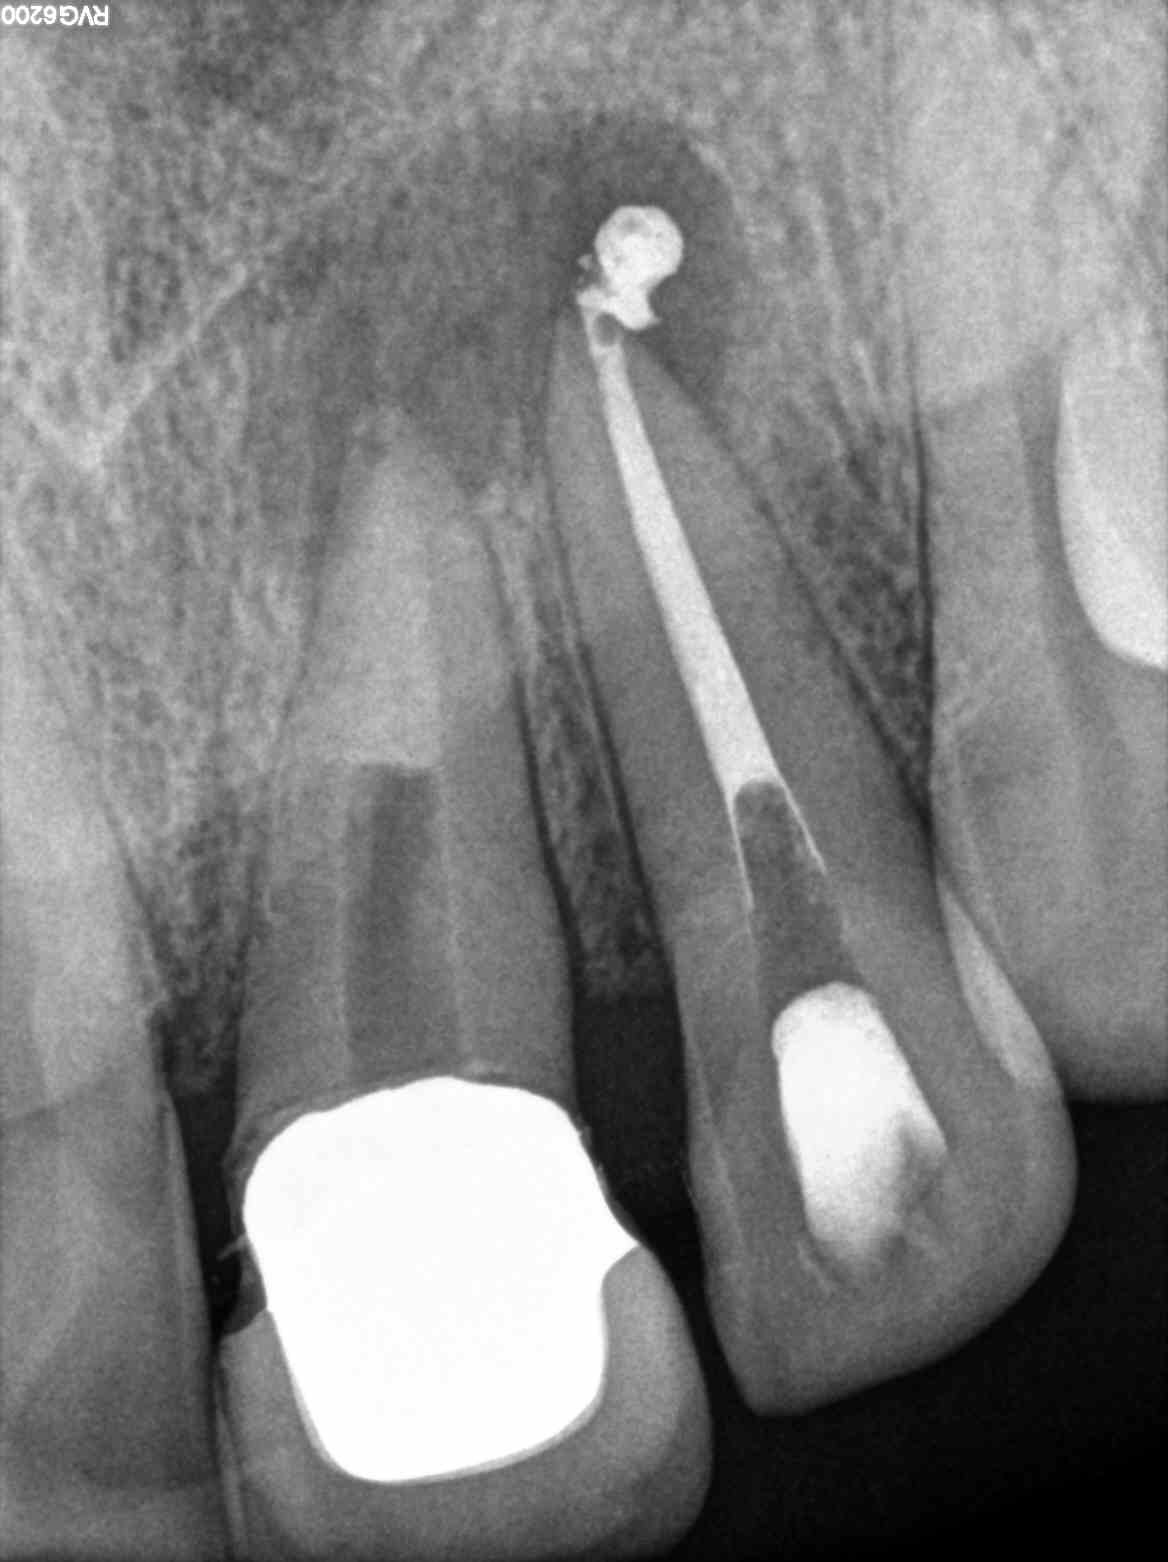

Reabsorción apical sellado con M.T.A. Endodoncia Badajoz Stop Apical Endodoncia The extent of the apical obturation when performing root canal therapy is a key factor that influences the success of the treatment. Root canal shaping in the age of minimally invasive endodontics (mie) technology. The data presented in this review can aid in. Traumatic injury to the surrounding (periapical) soft tissue should be avoided at all times. The concept of. Stop Apical Endodoncia.

PUFF APICAL EN ENDODONCIA Stop Apical Endodoncia Traumatic injury to the surrounding (periapical) soft tissue should be avoided at all times. This retrospective study evaluated cases of unintentional overfillings during root canal treatment for the fate of the extruded sealer and its influence on the outcome. The concept of instrumentation beyond the apical foramen by small flexible file. The extent of apical enlargement can impact the outcome. Stop Apical Endodoncia.

endodonciamississippi Endodoncia 12 con periodontitis apical cronica Stop Apical Endodoncia The data presented in this review can aid in. The concept of instrumentation beyond the apical foramen by small flexible file. To this end, instrument stops should be used and instruments should be. This retrospective study evaluated cases of unintentional overfillings during root canal treatment for the fate of the extruded sealer and its influence on the outcome. The extent. Stop Apical Endodoncia.